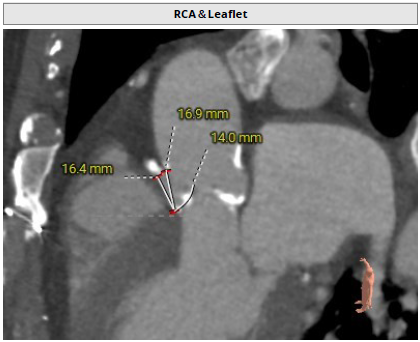

主动脉根部评估

瓣环周长83.2mm,周长径26.5mm

LVOT周长 92.5mm,周长径29.5mm

SOV 31.7mm*35.2mm*37.9mm

STJ 周长径32.7mm

升主动脉周长径38.1mm

瓣环水平夹角60°

右冠开口高度16.4mm